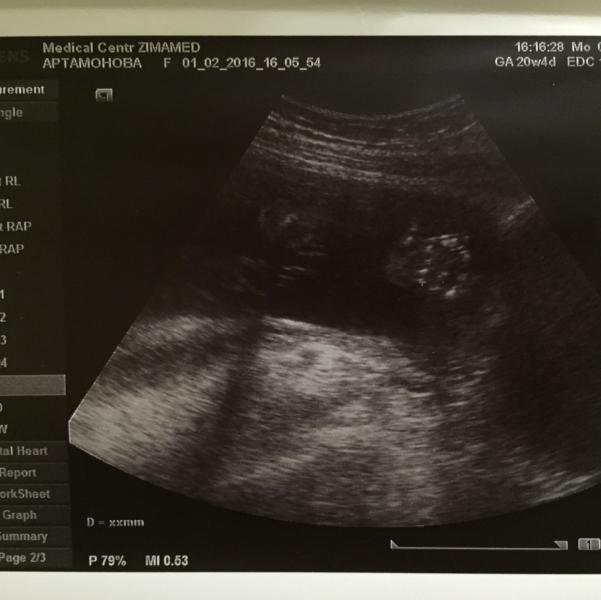

На картинке единственный приличный кадр с сегодняшнего УЗИ, наш кроха показал свою ладошку🙈🙈😍